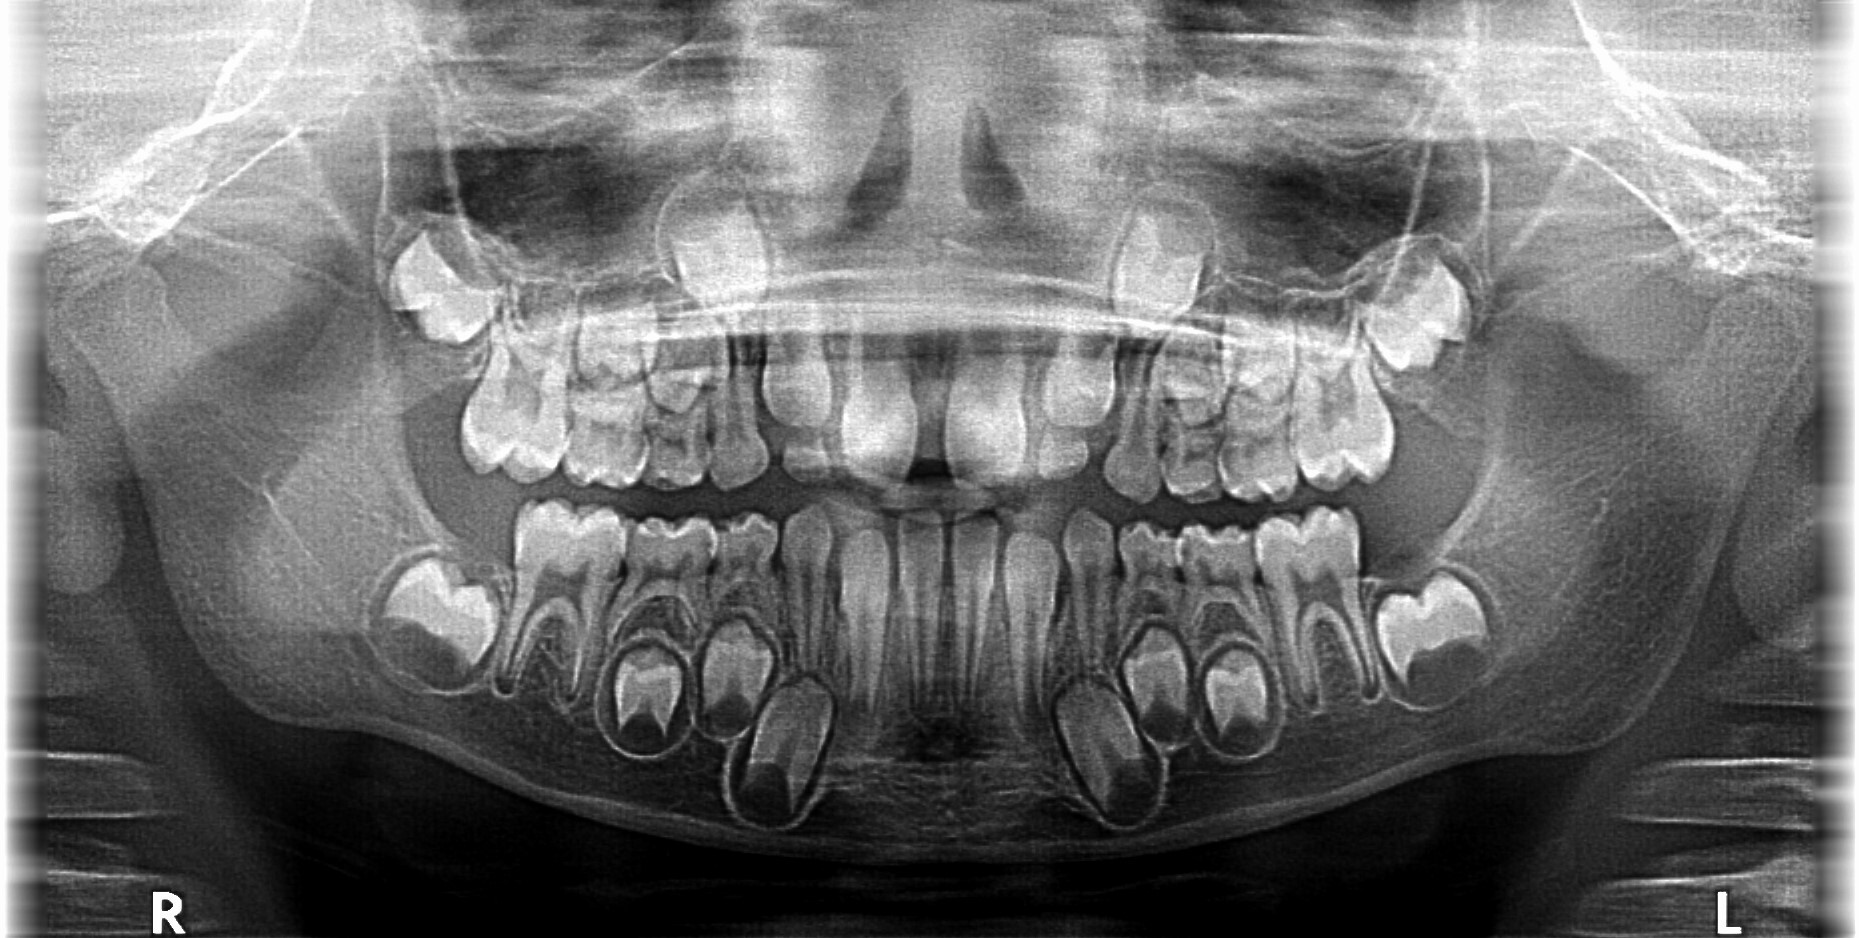

Нейросети помогают врачу анализировать изображения лица и зубных рядов для составления ортодонтического лечения. В рамках диагностики ИИ выявляет асимметрию, отклонение зубов от линии и скученность.

Искусственный интеллект, отметила ортодонт, анализирует фотографии, сделанные при хорошем освещении, и помогает выявить проблемы с прикусом.